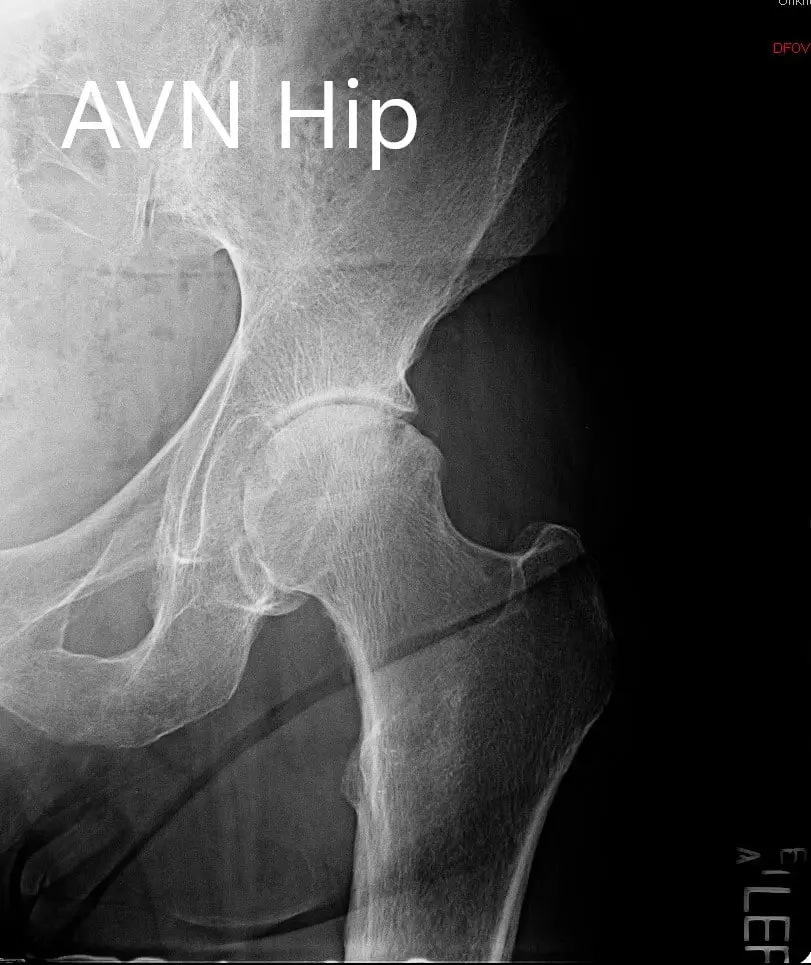

Imaging revealed severe osteoarthritis of the left hip and an MRI suggested avascular necrosis changes in the left hip. In view of lifestyle limiting hip pain and patients’ comorbidities, a robotic total hip replacement was advised to the patient. Risks, benefits, and alternatives were discussed at length with the patient. He agreed with the plan. A preoperative CT scan was also obtained.

Preoperative X-ray showing the AP and the lateral views of the left hip

PREOPERATIVE DIAGNOSIS(ES): Left hip arthritis secondary to avascular necrosis.